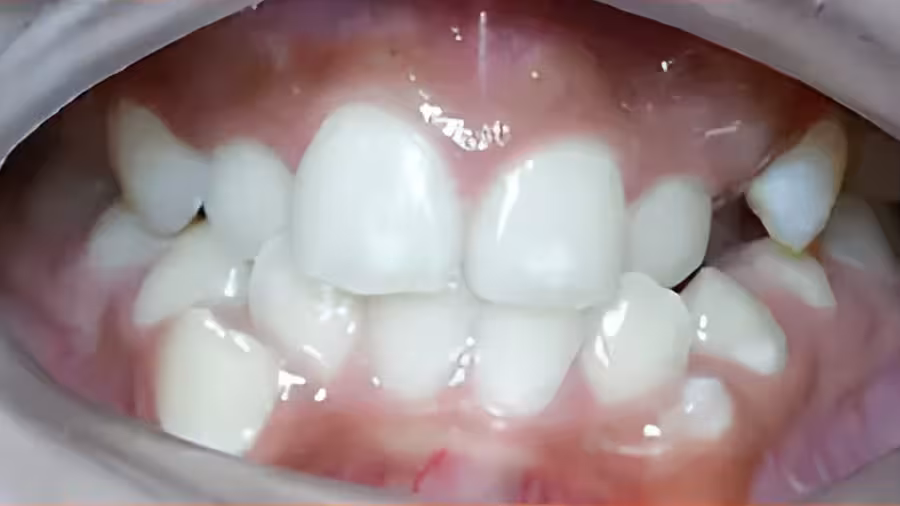

This patient had severe upper and lower crowding with impacted cuspids.